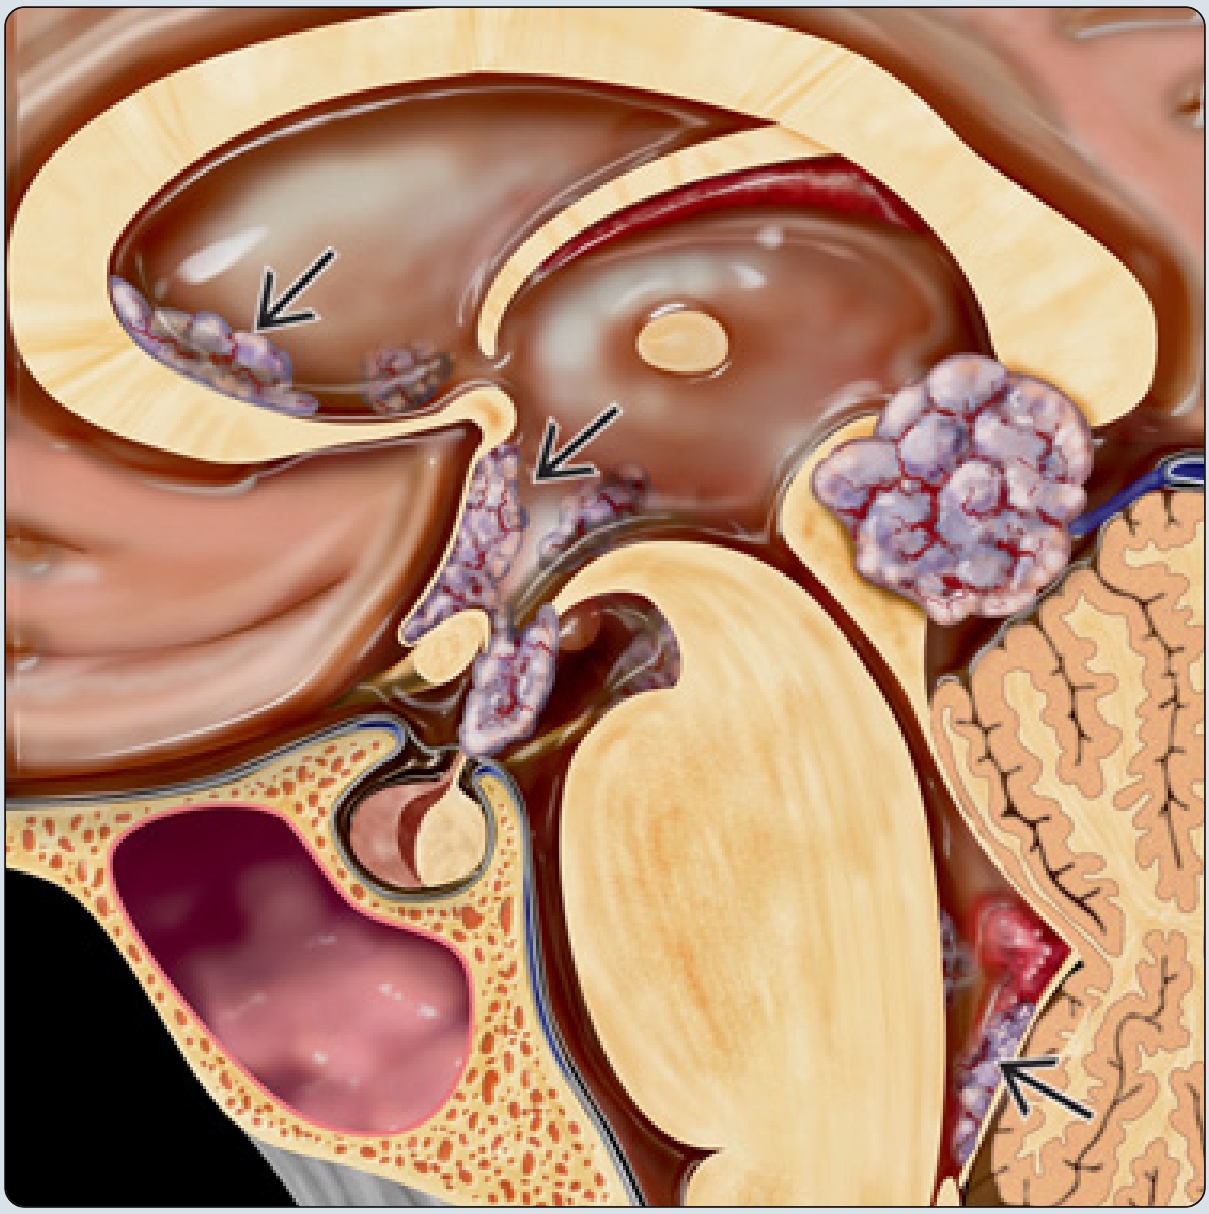

生殖细胞瘤还有两个好发部位,一个是松果体区,其常常包绕松果体本身钙化,而另一个好发部位是基底节区,其几乎只见于男性,其常伴患侧邻近脑实质、脑干萎缩,可见华勒氏变性。